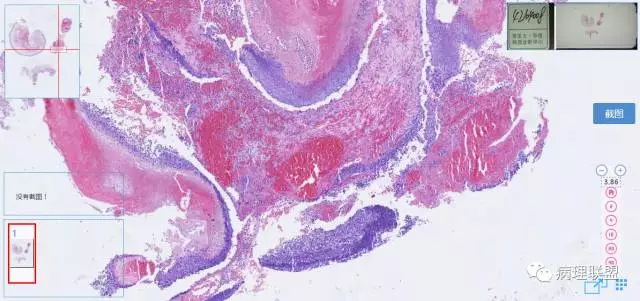

第二例

第一例和第二例病例我把典型图像压下来,是让我们以后注意,典型里找不典型,毛母质瘤主要由两种细胞构成,嗜碱细胞和影细胞构成,主要认识嗜碱细胞。